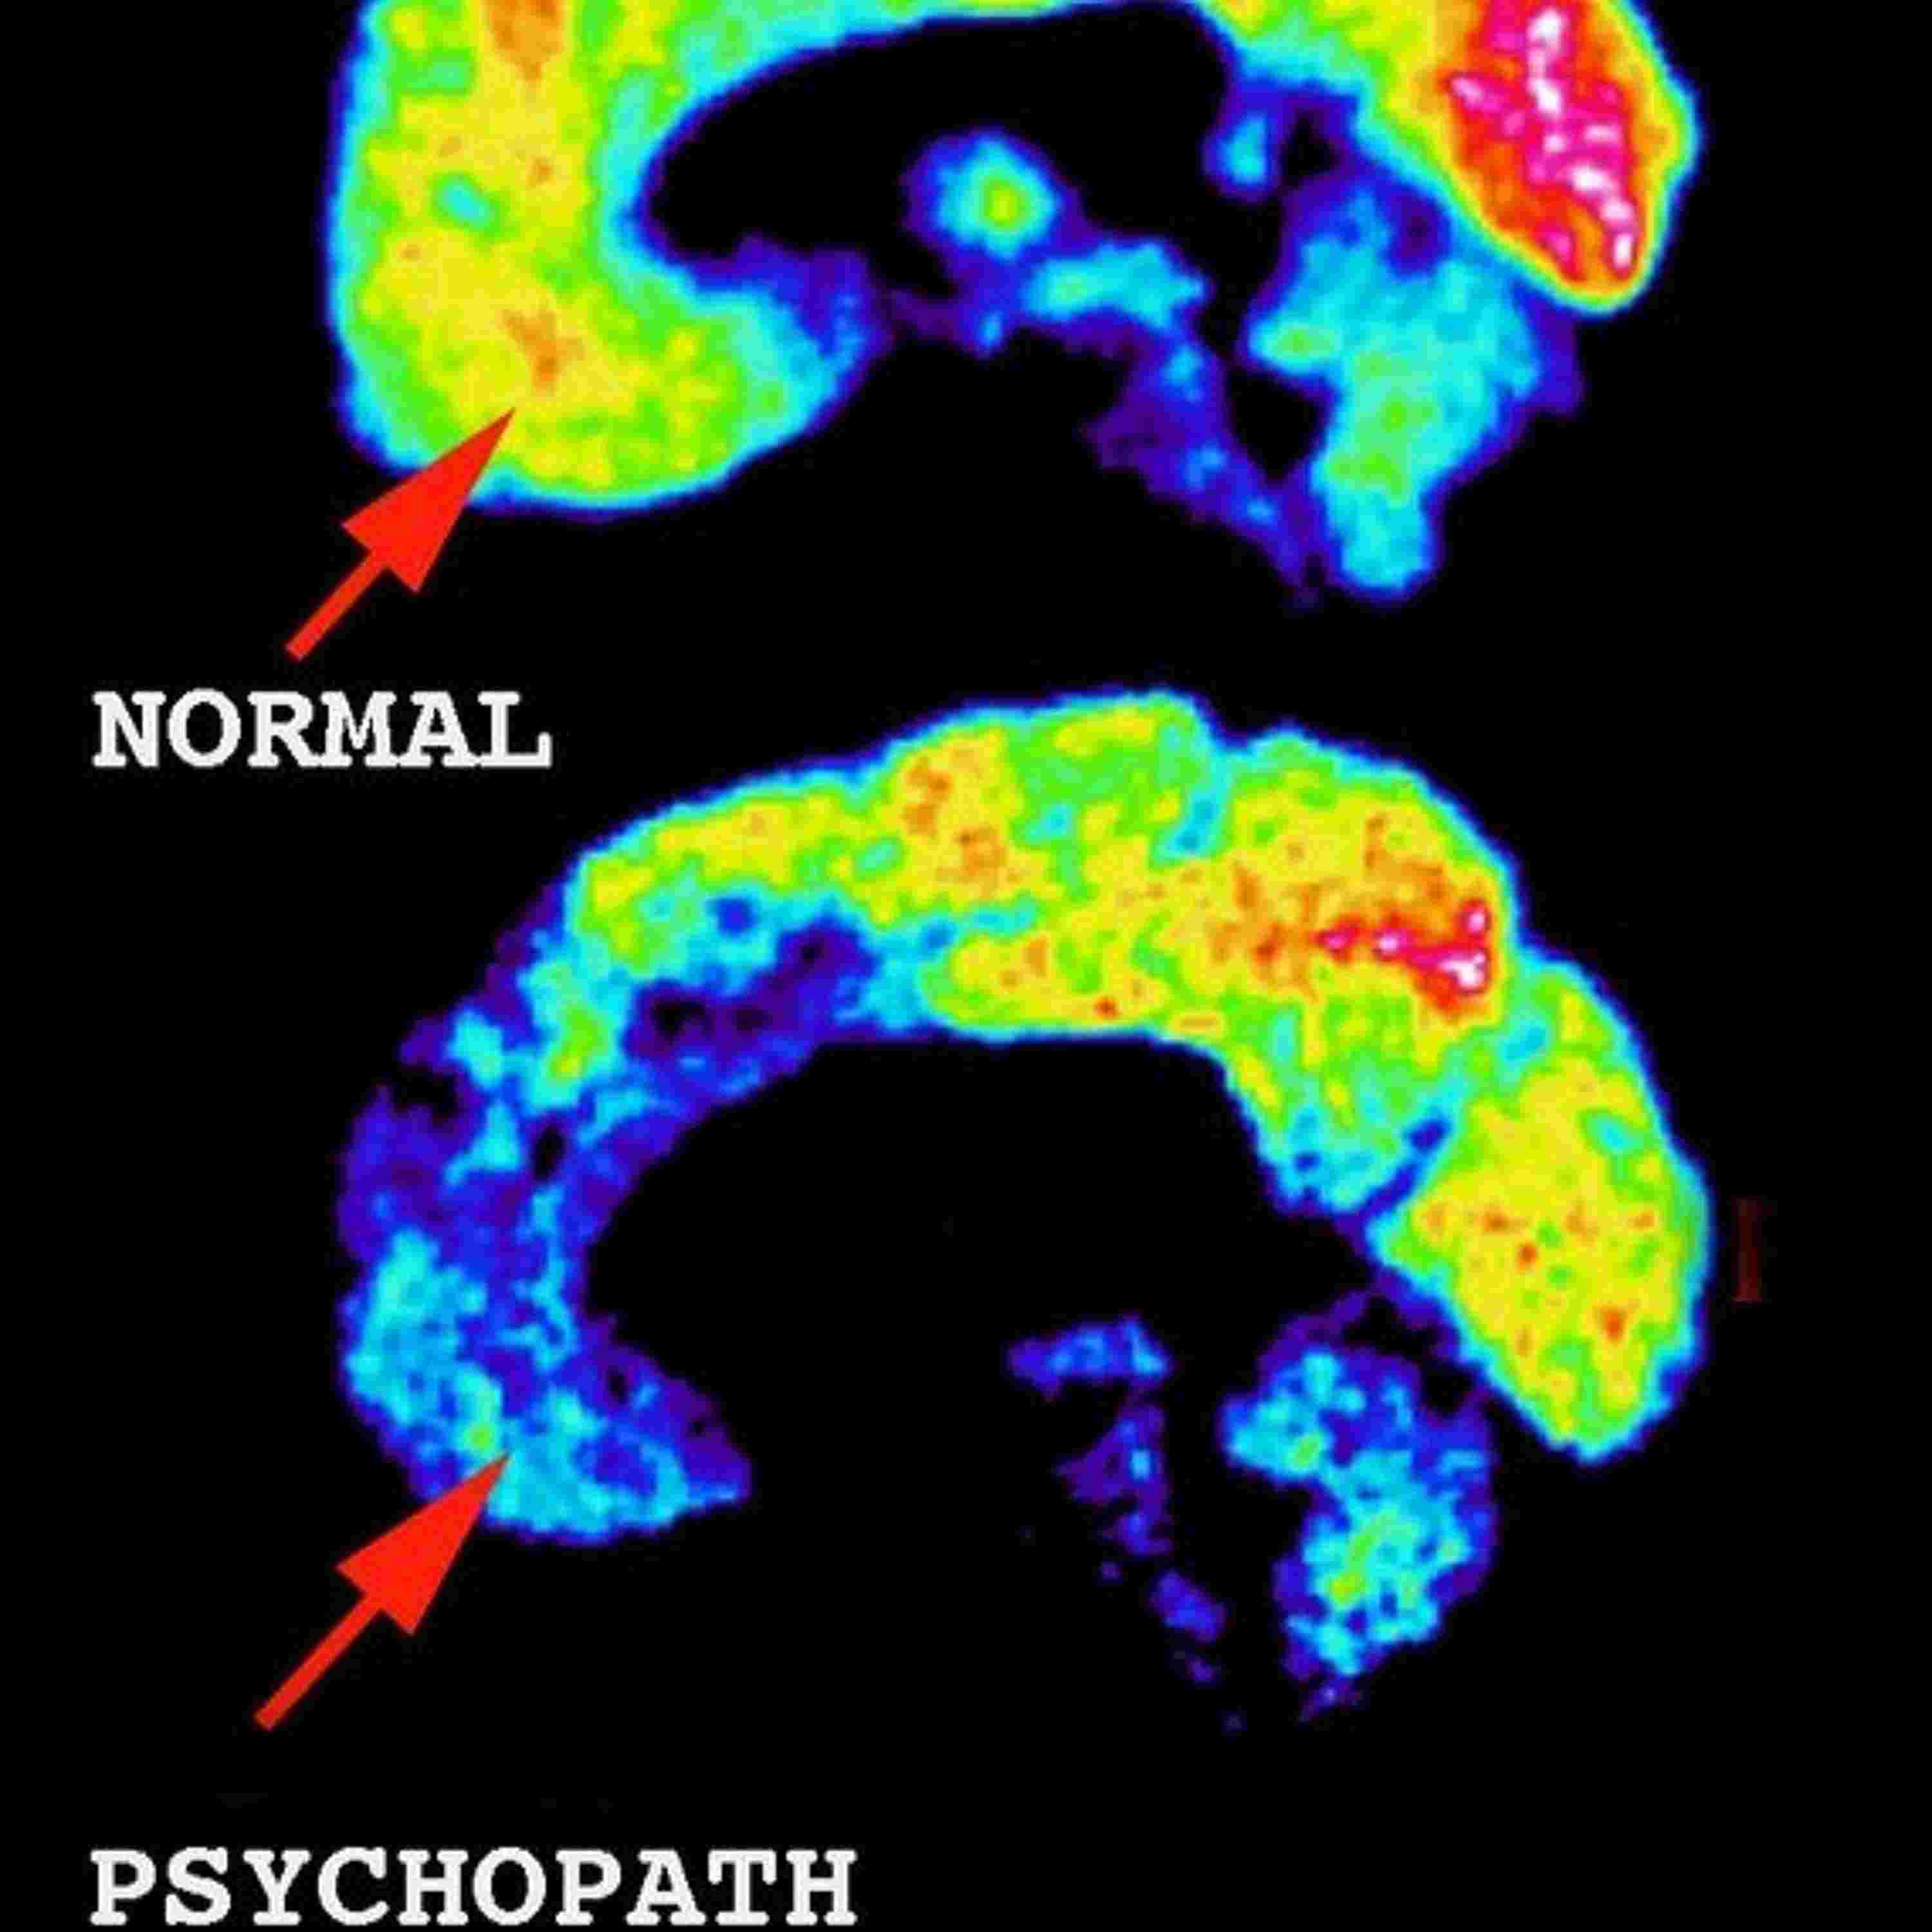

Ep. 23 Jim Fallon and the Psychopaths, Part 1

A neuroscientist makes an unsettling discovery.